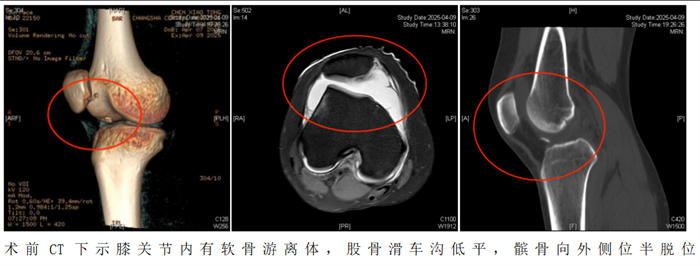

20岁的陈静怡(化名)在打篮球跳跃落地时,不幸发生右膝盖骨脱位。虽然后来自行复位,但随即出现右膝疼痛、肿胀及关节活动受限。经立博体育 检查诊断为“急性髌骨脱位,髌骨内侧、股骨外侧髁撕脱骨折”。通过微创手术,成功将“脱轨”的髌骨复位到“轨道”上。

“患者入院后,我们为她制定了周密的个性化治疗方案,采用‘关节镜下髌骨成形术+纽扣十字缝合法软骨修复术’帮助恢复膝关节功能。”据立博体育|实时赛事直播与比分|权威专家分析与体育竞猜平台 运动医学、创伤关节、骨病科主任丑克介绍,这项联合术式在省内少见,因患者游离软骨骨碎片大,软骨下骨骨质有血运,髌骨内下缘软骨缺损面积大,通过高强度缝线采用纽扣十字缝合法原位缝合剥脱的软骨块成形髌骨,犹如为膝关节打造了一个防护网。手术过程顺利,术后患者恢复良好。

2.如果出现以下情况需要考虑手术治疗。初次脱位后出现髌骨或股骨软骨骨折导致关节内出现游离体时,必须手术治疗。关节镜是目前成熟的关节内镜技术,医生通过内镜,直视下观察髌骨的损伤,取出游离体并修复软骨,行内侧支持带紧缩和外侧支持带松解术,即可取得满意的疗效。该手术是微创手术操作,创伤小,恢复快,多数患者术后第1天即可下地活动。